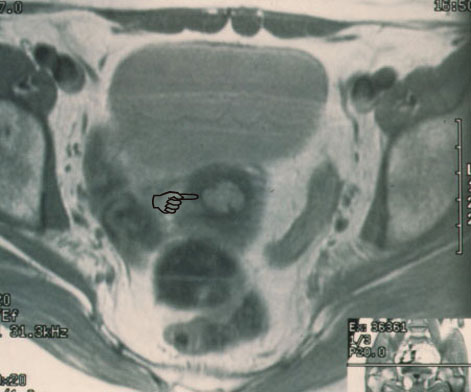

fig. 2

Figura 2.- RMN: Plano transversal con contraste, en el que se ve el endocervix engrosado (punta de dedo) y bien delimitado.